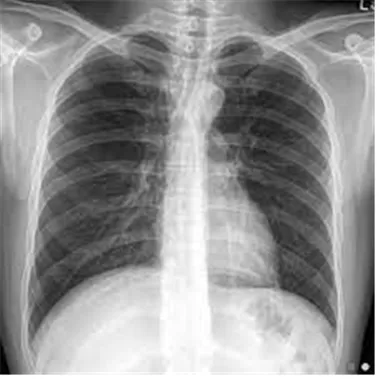

45세 여성이 3주 전부터 지속된 기침으로 내원했다. 초기에는 인후통과 콧물이 동반되었으나, 이후 점차 호전되었다. 환자는 3년 전부터 류마티스 관절염으로 치료를 받고 있으며, 최근 증상이 악화되어 바이오로직스 치료를 고려 중이다. 비흡연자이며, 과거에 결핵 치료 경험은 없다. 폐 진찰에서 특이 소견은 발견되지 않았다. 가래 검사와 혈액 검사 결과, 그리고 가슴 X선 사진을 바탕으로 한 처치 방안은 무엇인가?

가래: AFB smear (-), TB PCR (-)

혈액: 인터페론감마방출검사 (+)

류마티스관절염을 치료하기 위한 생물학적제제(anti-TNF-a)를 사용하면 면역억제를 통한 잠복성 결핵의 활성화, 결핵의 중증도 악화 위험으로 사용하기 전에 결핵에 대한 검사를 시행한다. AFB와 TB PCR, CXR에서 음성이었고, IGRA에서 양성이기 때문에 잠복결핵이다.